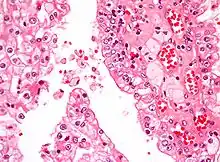

The most common type of kidney malignancy is renal cell carcinoma,[31] which is thought to originate from cells in the proximal convoluted tubule of the nephron.[12][32] Another type of kidney cancer although less common, is transitional cell cancer (TCC) or urothelial carcinoma of the renal pelvis.[33] The renal pelvis is the part of the kidney that collects urine and drains it into a tube called the ureter.[33] The cells that line the renal pelvis are called transitional cells, and are also sometimes called urothelial cells. The transitional/urothelial cells in the renal pelvis are the same type of cells that line the ureter and bladder. For this reason TCC of the renal pelvis is distinct from RCC and is thought to behave more like bladder cancer.[33] Other rare types of kidney cancers that can arise from the urothelial cells of the renal pelvis are squamous cell carcinoma and adenocarcinoma.[12]